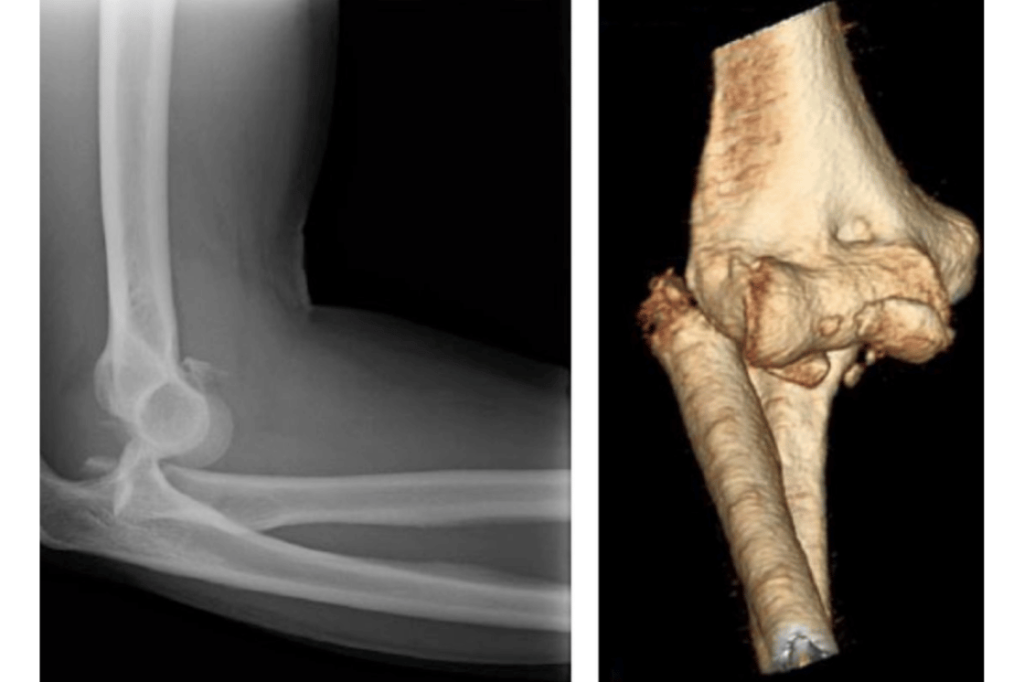

Dirsek çıkığı, dirseği oluşturan kemiklerin (humerus, radius ve ulna) eklemden ayrılmasıyla oluşur. Tek başına çıkık olduğunda kapalı redüksiyon (yerine oturtma) ile tedavi mümkünken, eğer bu duruma kemik kırıkları eşlik ediyorsa durum kompleks dirsek travması olarak adlandırılır ve genellikle cerrahi tedavi gerektirir.

Kompleks travmalar genellikle radius başı kırığı, koronoid çıkıntı kırığı, olekranon kırığı veya bu yapılarla birlikte ligament yaralanmaları içerir. Bu tür kombinasyonlara “terrible triad” (korkunç üçlü) gibi isimler de verilir. Bu durumlar doğru tedavi edilmezse, eklemde kalıcı instabilite (fazla oynaklık), kısıtlı hareket açıklığı ve ağrıya yol açabilir.